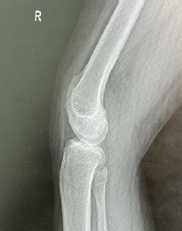

Rare Periprosthetic Fractures Following Oxford Unicompartmental Knee Arthroplasty: A Case Series of Supracondylar Femoral and Proximal Tibial Fractures

Amyn M Rajani , Vishal Kulkarni , Clevio Desouza

………………………………p.164-169